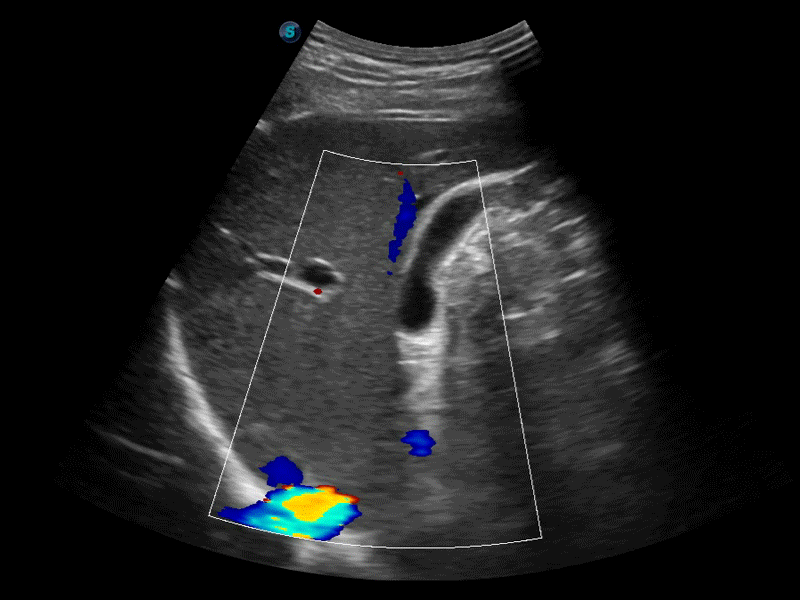

高分辨率血流成像技術(shù)提高了對(duì)低速血流信號(hào)的檢測(cè)能力。在提高空間分辨率的同時(shí),也克服了血流外溢現(xiàn)象,為用戶提供更加真實(shí)的血流動(dòng)力學(xué)信息。